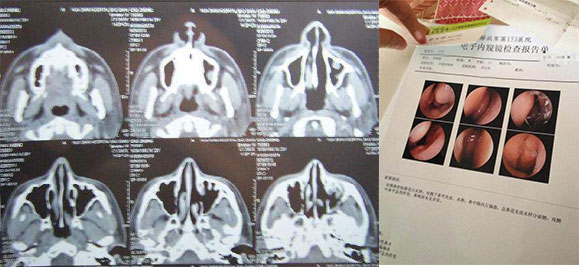

我把我的病情情况详细的跟老师说了,然后把我在医院的检查单子都发给老师看了,老师非常有耐心的跟我说我的鼻炎情况。他说我最早的时候错把鼻炎当成感冒耽误治疗,之后在鼻炎早期的时候不重视治疗。后期治疗方法不当导致引发鼻窦炎,还说我自己瞎乱用药,他告诉我西药和喷剂当中都是含有麻黄素或者抗阻胺类的,只能够是暂时缓解鼻炎症状,效果会越来差而且之后会导致更严重的病状,连续使用会导致药物性鼻炎。他说我鼻炎患者常犯的几个错误都让我占了,然后给我指导治疗鼻炎。

听老师这样一讲,非常专业感觉挺靠谱的,我决定试一试。反正死马当作活马医吧,都已经这样了也不差再尝试这一次,万一治好了呢?由于老师是郑州中医院的,距离比较远,就让老师给我发的顺丰快递,第二天就寄到了。当天晚上我迫不及待的打开使用。放鼻子里1个多小时,使用完拿掉之后当时就从鼻子里流出来好多的鼻涕,比平时流的鼻涕多好多而且还不一样。当时就微信问了老师,老师就说这是在排除鼻腔内部的细菌病毒,排除后鼻炎就会逐渐好转。你还别说当时鼻子就通顺好多,当天晚上还睡了个好觉。这第一次使用就给了我非常好的感觉,自己明显可以感觉到那个治疗的效果,真是跟吃药和喷剂不一样。就这样我使用了2天后,我明显发现我的喷嚏减少了,不像之前一连串的打喷嚏,鼻涕也减少很多,整个鼻子通顺了。然后我用了整整一个星期后,喷嚏不打了、鼻涕也没有了,关键是我的头疼也好转了,整个鼻炎感觉像完全好了一样。明显感觉整个人比之前轻松了好多,效果真是太好了,要不是我自己使用知道,别人说的话打死我都不会相信。于是我就去医院做了一个检查,医生说鼻炎的情况基本已经消失,听到这我看着检查的单子当时就开心的笑了。怎么都没想到,这么多年的鼻炎想尽各种方法都没有治好 ,这下终于治好了!